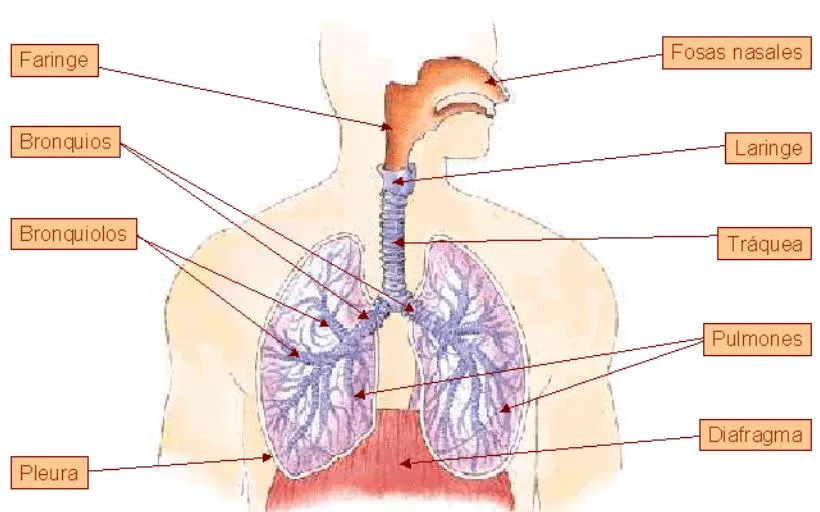

Esquema del sistema respiratorio con los nombres de sus partes ...

Indica el motivo para eliminar esta imagen: